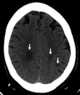

Diffuse cerebral calcification